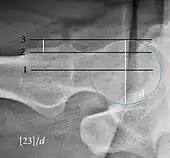

Radiograph of a cam type impingement.

Projectional radiography ("X-ray")is often considered first line for FAI.[10] Anterior-posterior pelvis and a lateral image of the hip in question should be attained.[10] A 45-degree Dunn view is also recommended.[10][19]

Measurements of impingement on X-ray.[notes 1][20]

MeasurementImageTargetNormal value

Center-edge angle of Wiberg

The superior-lateral coverage of the femoral head.

• >20° (<55 years old)[notes 2]

• <24° (>55 years old)[notes 2]

• >40° indicates overcoverage

Crossing ratio Percentage of acetabular walls crossing. Normal acetabulum is oriented in anteversion. Its value ranges from 15 to 20° in the equatorial plane of the acetabulum and decreases gradually towards the acetabular roof, where normal values range from 0 to 5°. Retroversion of the upper part of the acetabulum has been related with pincer type impingement. In radiography the presence of a "crossover sign" is produced when the posterior wall of the acetabulum crosses the anterior wall before reaching the acetabular roof. It is a sign of acetabular retroversion and it has been linked with overcoverage and pincer impingement. Nevertheless, this sign has been described in 6% of the normal population. Therefore, more important than its presence is the percentage of crossing. <20%

• Higher is significant crossing

Alpha angle

Measured in 45° Dunn view.

Degree of bulging of the femoral head-neck junction: In normal conditions there is a symmetric concave contour at the junction of the femoral head and neck. Loss of this concavity or bone bulging may lead to cam type impingement. The degree of this deformity can be measured by the alpha angle. Although it can be measured in the cross-lateral view, the 45° Dunn view is considered more sensitive and the frog leg view more specific in determining pathologic values.

• Normal: ≤68° in men, ≤50° in women

• Borderline: 69° to 82° in men, 51° to 56° in women

• Pathological: ≥83° in men and ≥57° in women

Femoral head-neck offset

Measured in cross-lateral view.

Offset of the femoral head with regard to most prominent aspect of the femora neck>10 mm

Offset percentage Femoral head-neck offset related to femoral head diameter >0.18

• less indicates high risk of cam type impingement

Tönnis angle Slope of the sourcil (the sclerotic weight-bearing portion of the acetabulum) 0 to 10°

• >10° is a risk factor for instability

• <0° is a risk factor for pincer impingement

Caput-sourcil angle[21] Superior to the Tönnis angle in cases without joint space narrowing or subluxation.[21] The medial point of the sourcil is at the same height as the most superior point of caput femoris. −6 to 12°[21]

• >12° is a risk factor for instability

• <-6° is a risk factor for pincer impingement